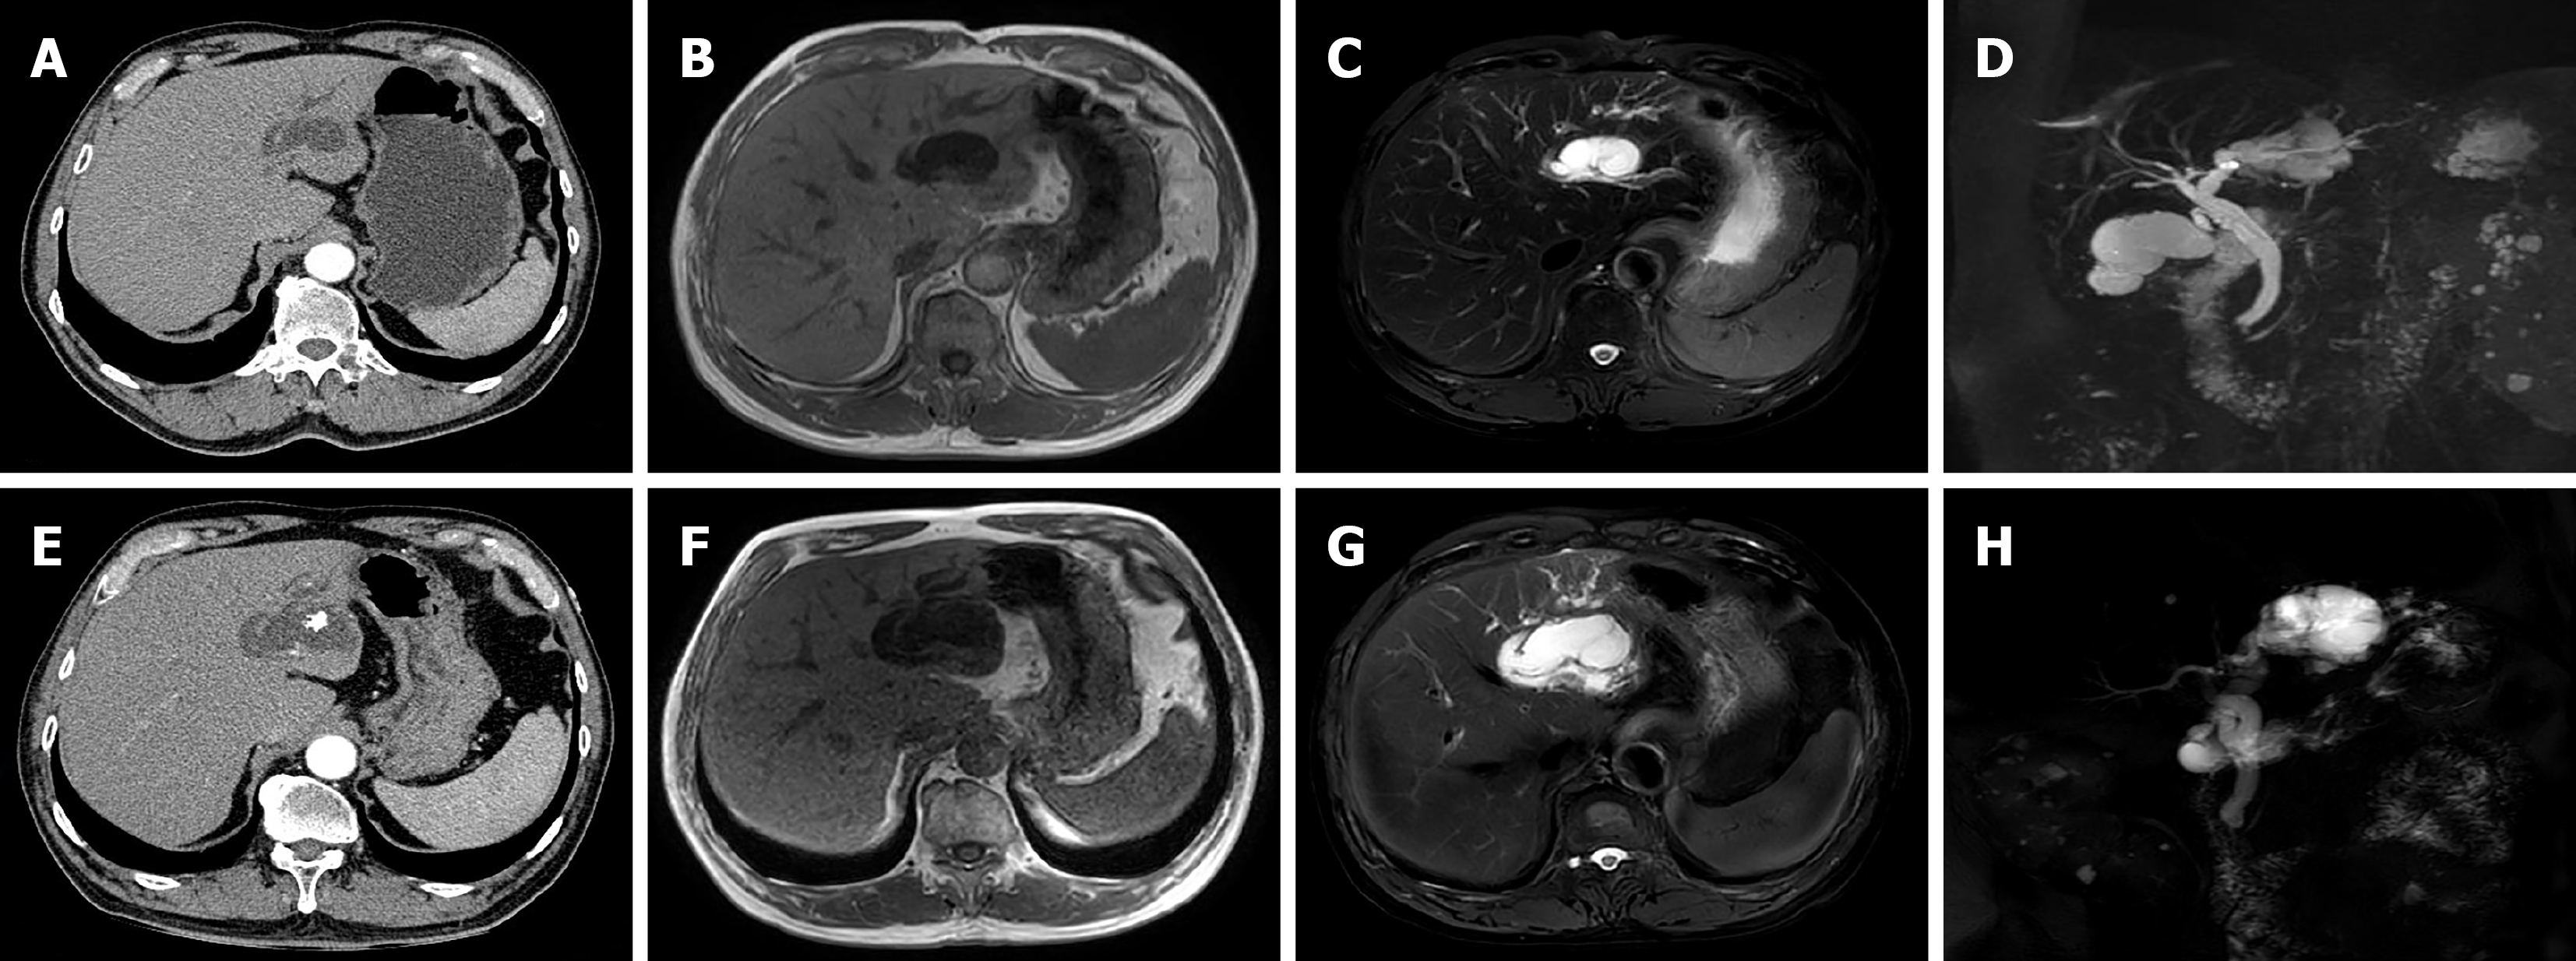

Abdominal ultrasound revealed dilatation of the common bile duct with multiple stones, dilatation of the left intrahepatic bile duct with multiple stones, adenomyosis of the gallbladder, and multiple crystals in the gallbladder. Enhanced CT images captured four years prior to admission revealed cystic dilatation of the left intrahepatic bile duct, with a size of approximately 41 mm × 22 mm, stones in the left intrahepatic bile duct, and adenomyosis at the fundus of the gallbladder (Figure 1A). MR images revealed dilatation of the left intrahepatic bile duct, local cystic dilatation, and stones in the left intrahepatic bile duct (Figure 1B-D). After admission, enhanced CT images captured in the arterial phase revealed cystic dilatation of the left hepatic duct, with a size of approximately 63 mm × 51 mm, numerous papillary nodules, stones in the left intrahepatic bile duct, and common bile duct dilatation (Figure 1E). MR images revealed cystic dilatation of the left hepatic duct with papillary nodules, stones in the left intrahepatic bile duct, common bile duct dilatation, and stones in the common bile duct (Figure 1F-H). Endoscopic retrograde cholangiopancreatography (ERCP) revealed that the duodenal papilla was enlarged and protruded into the intestinal cavity. However, there was no surface erosion and no visible tumour. The papillary orifice was significantly dilated, with a fish-mouth appearance. A large amount of translucent and jelly-like mucus was continuously oozing from the duodenal papilla. Cholangiography revealed significant dilatation of the common bile duct and multiple cloudy, irregular filling defects in the extrahepatic bile duct. During the clearing of the bile duct with the balloon catheter, the morphology and location of the filling defect in the bile duct were altered, and a large amount of translucent jelly-like mucus containing bile flowed out from the swollen duodenal papilla (Figure 2). The equipment we used was video duodenoscope (Olympus, JF-260V) and C-arm machine (GE HealthCare, OEC Elite). The wire-guided cannulation technique was selected. For this patient with IPMN-B, the papillary orifice was relatively large, making cannulation not particularly challenging. And during ERCP, a bile duct stent was placed to minimize post-ERCP cholangitis risk.